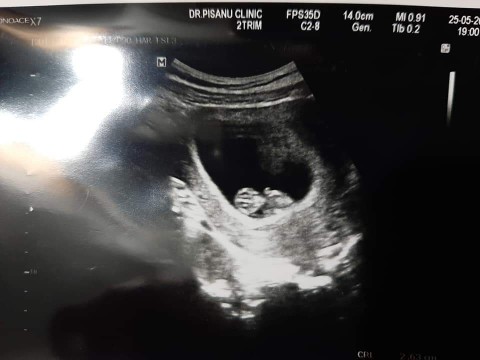

อันนี้ของเราตอน10wคะ